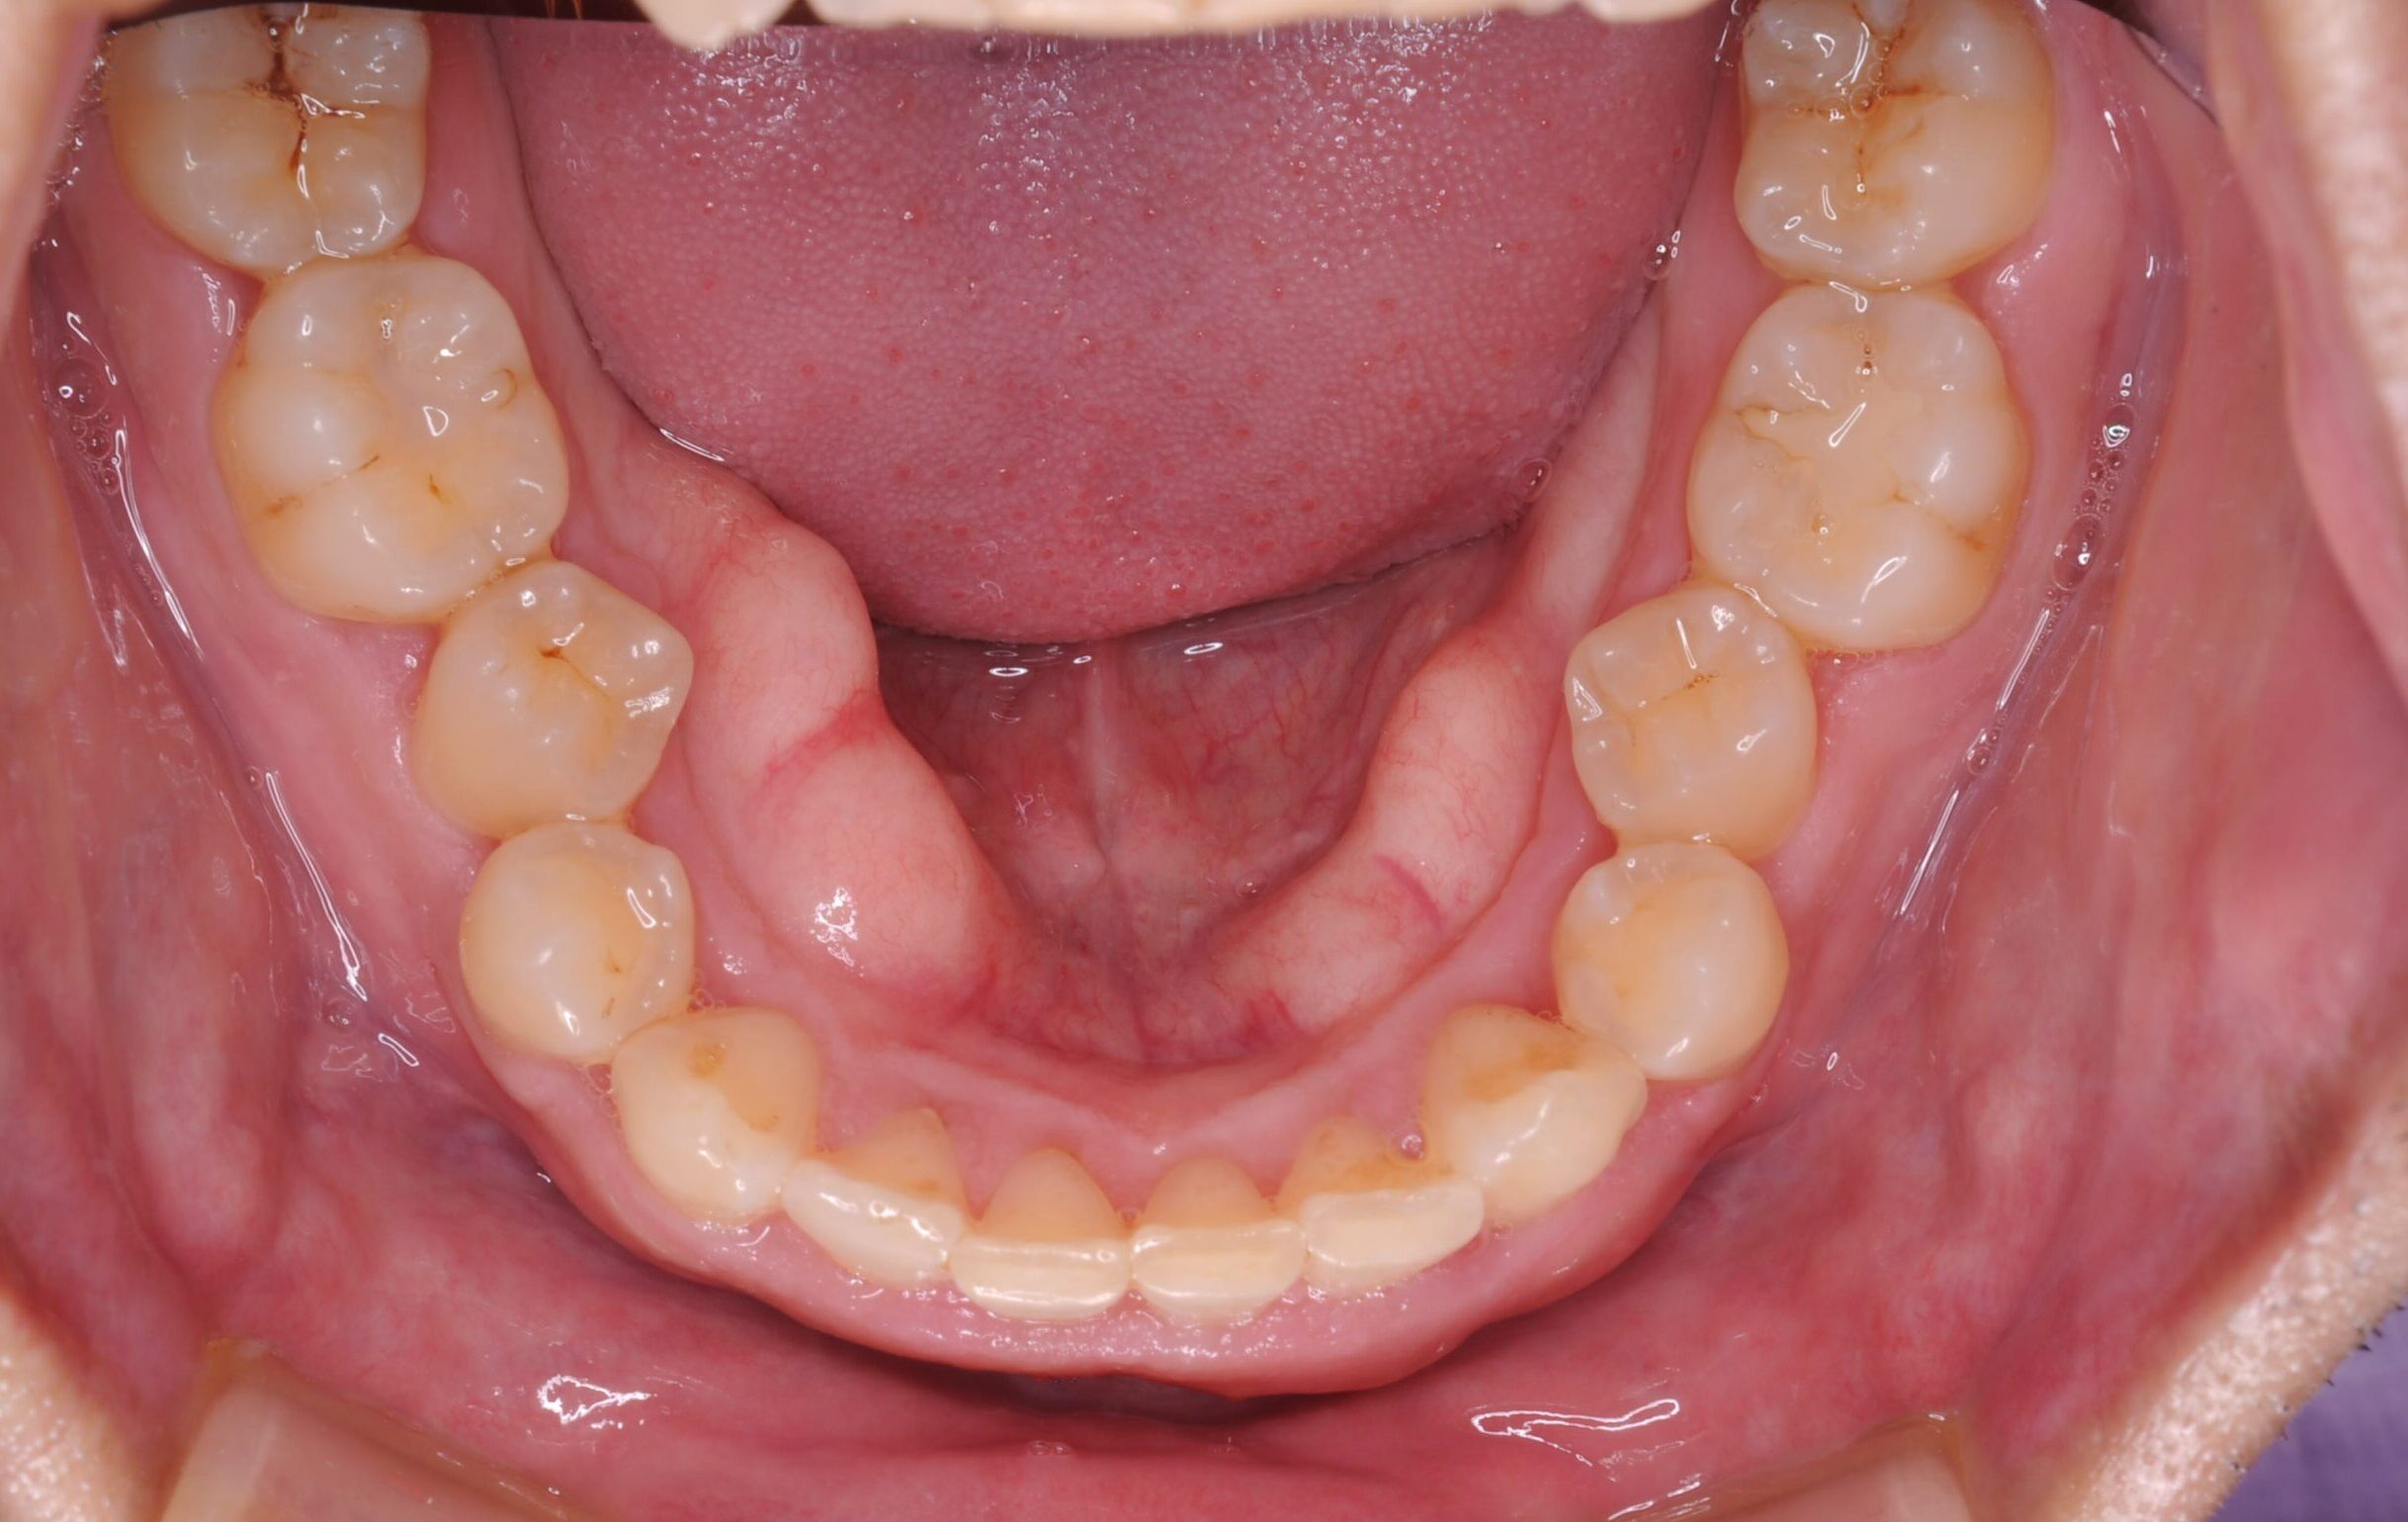

症例写真 after